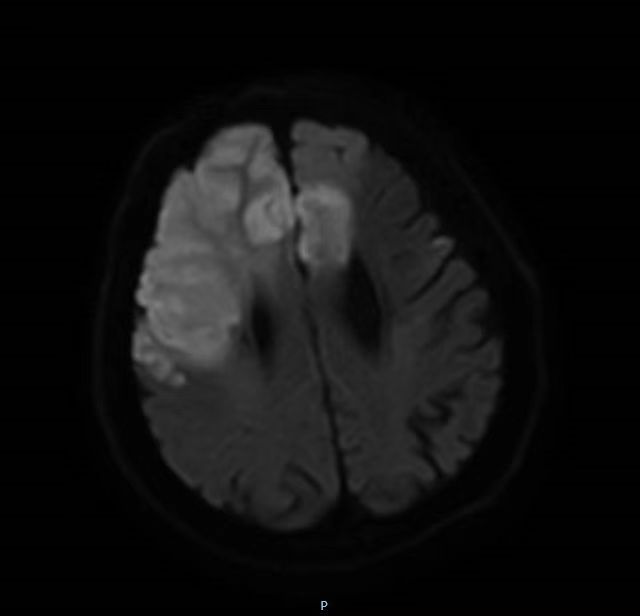

据了解,李先生入院时呈深昏迷状态,双眼向右凝视,左下肢肌力0级,左上肢肌力3级,右侧肢体肌力3级。左侧病理征阳性。急诊颅脑CT提示多发性脑梗死。MRI提示左侧额叶、右侧额颞顶叶及右侧基底节区大面积急性脑梗死,情况非常危急。

颅脑核磁共振提示大面积急性脑梗死。